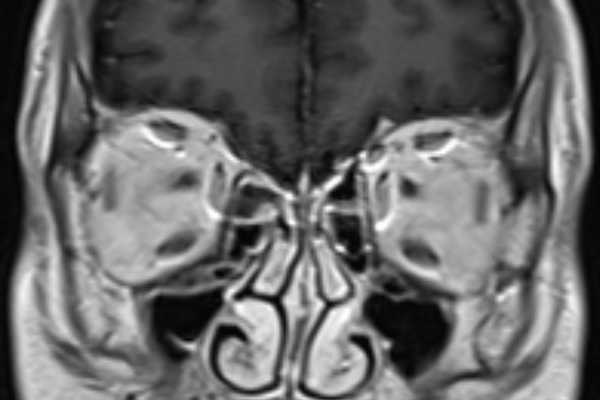

- This is a case of neurosarcodosis with pachymeningial involvement of the right tentorium. There was suspected involvement of the trochlear nerve (CN IV) in this region with resulting atrophy of the right superior oblique muscle.

- The trochlear nerve is the only cranial nerve to decussate. After decussating in the superior medullary velum it courses anterolaterally within the ambient cistern and along the free edge of the tentorium. It then travels in the lateral wall of the cavernous sinus and enters the orbit via the superior orbital fissure. It innervates the superior oblique muscle. It does not course in Dorrelo’s canal (CN VI does).